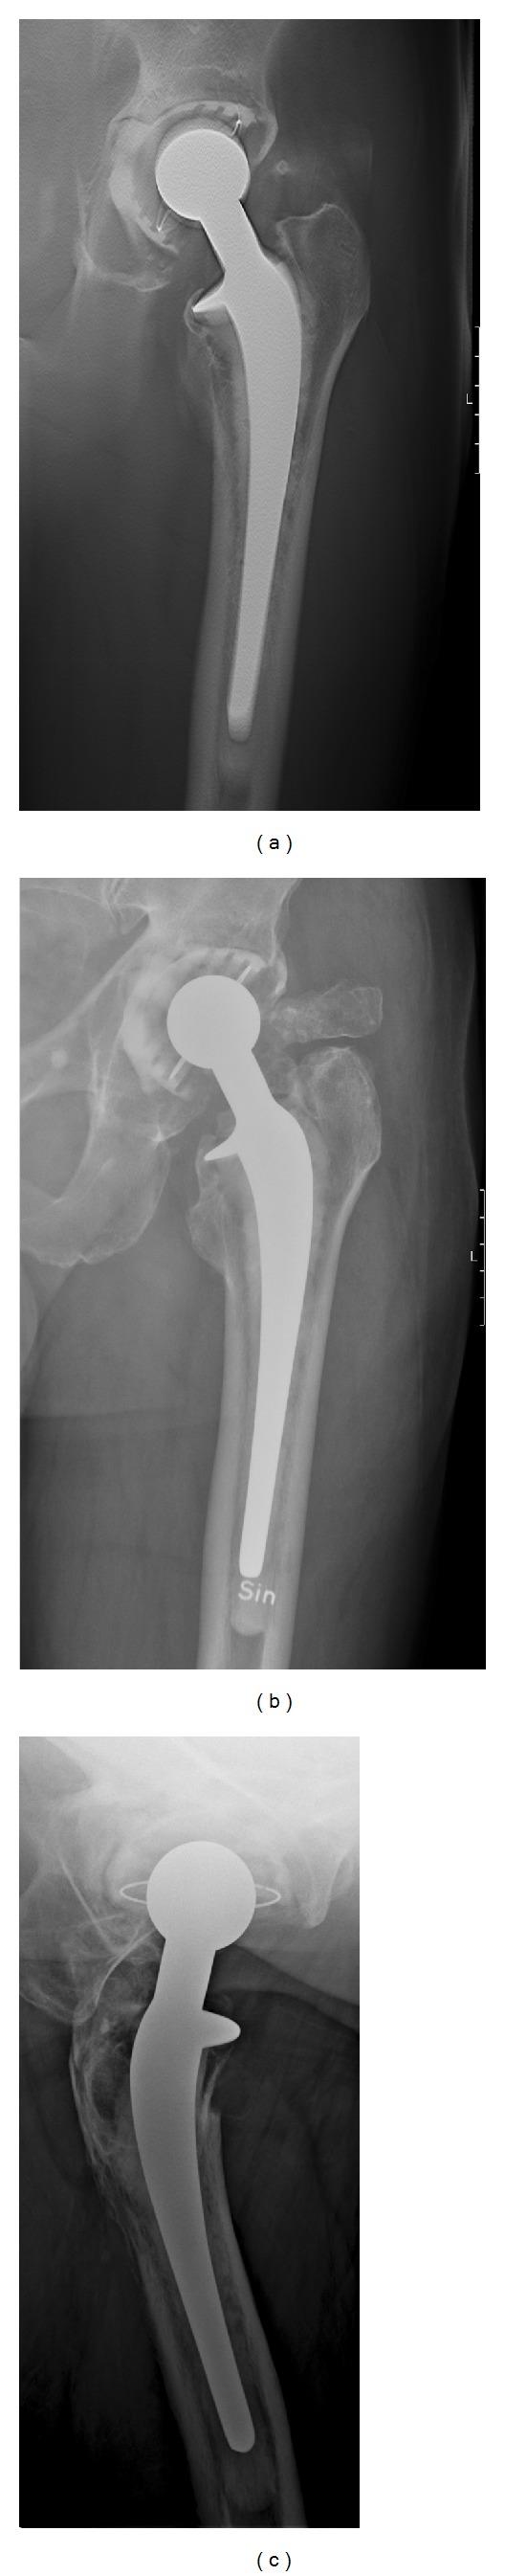

In a prospective study, radiography and digital tomosynthesis were performed in 40 consecutive patients with total hip arthroplasty referred for suspect prosthesis loosening. Tomosynthesis images were compared to anterior-posterior (AP) and cross-table lateral radiographs regarding demarcation and extent of demineralization and osteolysis. Further noted were skeletal fractures, cement fractures, fragmentation, and artifacts interfering with the diagnosis.

Tomosynthesis was superior to radiography with sharper delineation of demineralization and osteolysis in the AP projection. A limitation was the inability to generate lateral tomosynthesis images, with inferior assessment of the area anterior and posterior to the acetabular cup compared to cross-table radiographs. Artifacts interfering with diagnosis were found in one hip.

在一项前瞻性研究中,对 40 例全髋关节置换术后怀疑假体松动的患者进行了 X 线摄影和数字断层合成检查。断层合成图像与前后位(AP)和交叉位侧位 X 线片进行比较,以评估脱矿质和溶骨的界限和范围。还注意到了骨骼骨折、骨水泥骨折、碎裂和干扰诊断的伪影。

断层合成在 AP 投影中比 X 线摄影更能清晰地显示脱矿质和溶骨。局限性在于无法生成侧位断层合成图像,与交叉位 X 线片相比,对髋臼杯前后区域的评估较差。在一个髋关节中发现了干扰诊断的伪影。